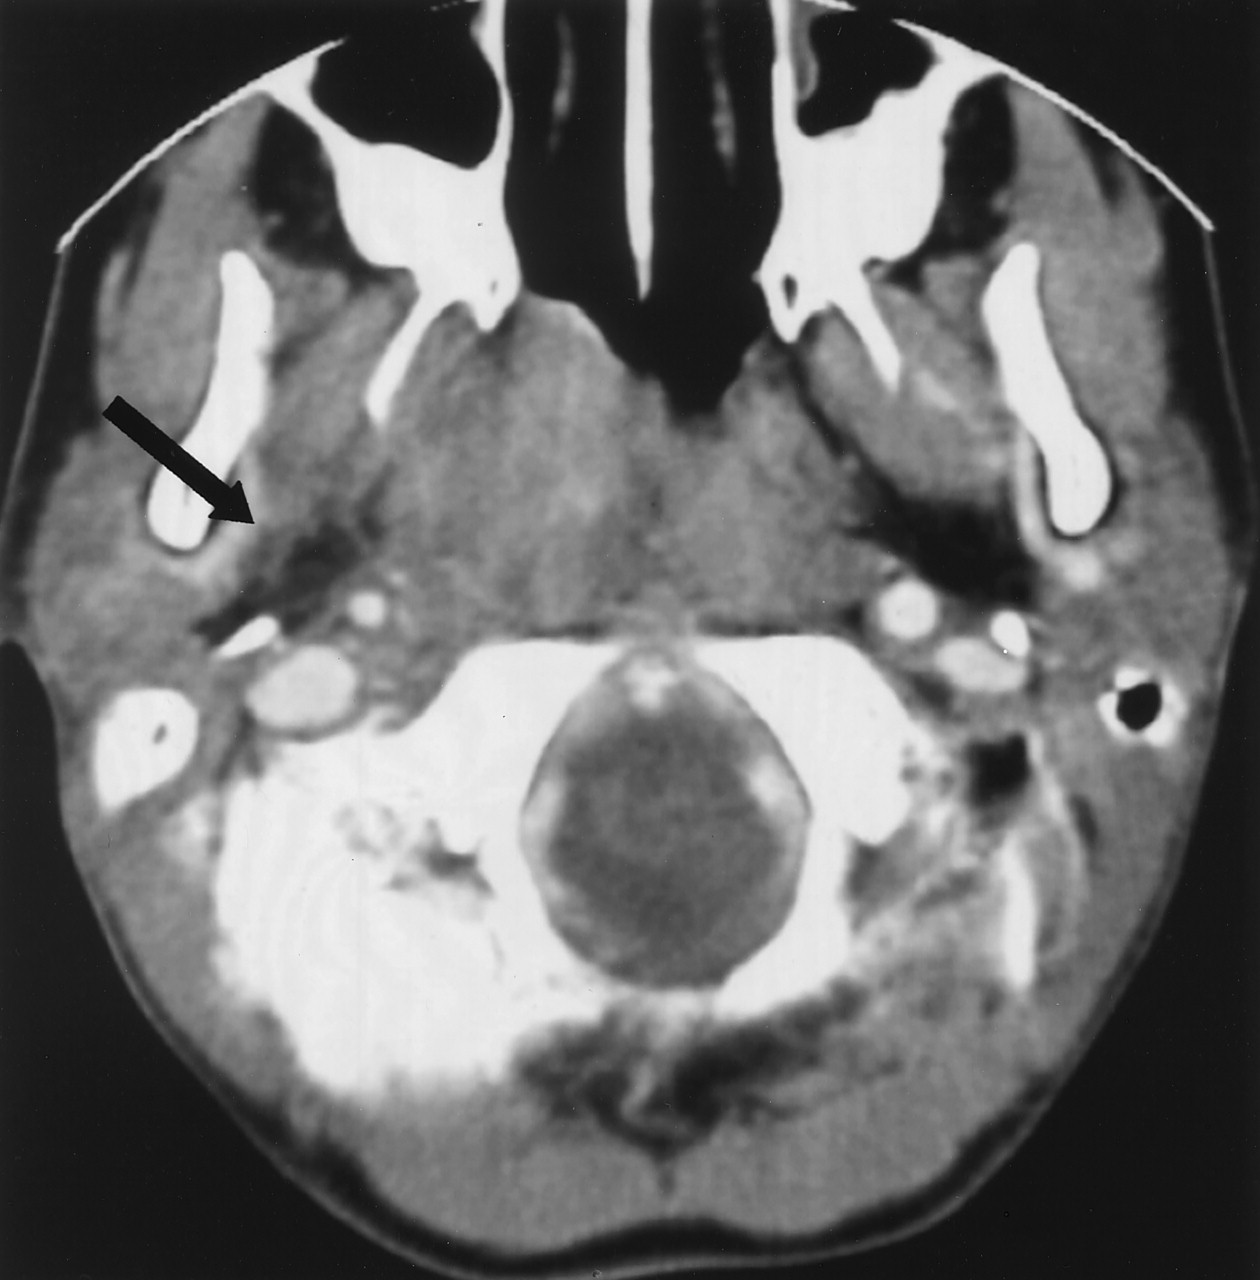

Gross parapharyngeal space invasion was present in just over one half of our patients (Fig 4). More subtle involvement of the parapharyngeal space may be difficult to appreciate, especially if the radiologist does not have NPC on the list of differential diagnoses. Norton et al (12) have suggested that violation of the nasopharyngeal plexus that appears as an enhancing line around the pharyngobasilar fascia may be indicative of an infiltrative tumor. Tumor can also extend to the pterygopalatine fossa causing widening that is easy to detect on CT (Fig 5) and MRI. This finding is however, not common and occurred in less than 20% of our patients. Finally, on rare occasions the tumor can spread into the masticator space to involve the muscles of mastication (Fig 6).

Invasion of the right parapharyngeal space fat. Axial contrast enhanced neck CT.